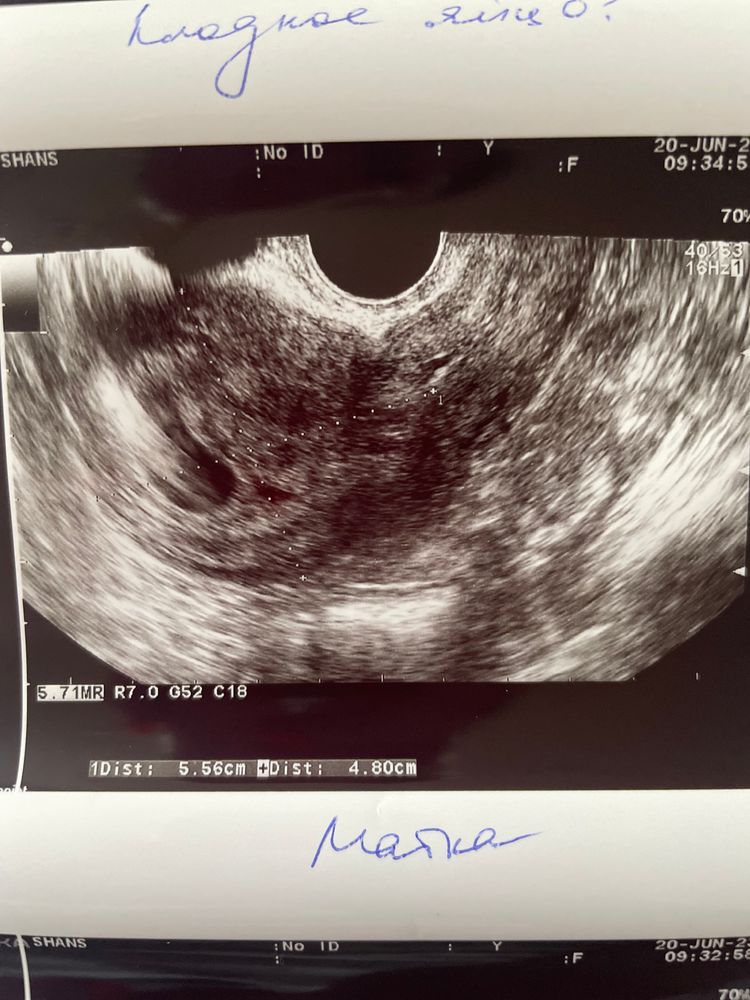

Повторное узи при пустом плодном яйце

То ли фото не очень качественные, то ли.. на первых двух снимках мне больше видятся сгустки крови. На третьем действительно похоже на плодное яйцо (но и гематомы бывают такой формы). На 28 ДПП как минимум должны были увидеть желточный мешок в плодном яйце. А так обычно эмбрион с СБ+. Можно еще несколько дней подождать и переделать УЗИ, лучше прям хорошего узиста и аппарат найти.

История ЭКО. 6н3д. Как определяют соответствующий срок УЗИ?